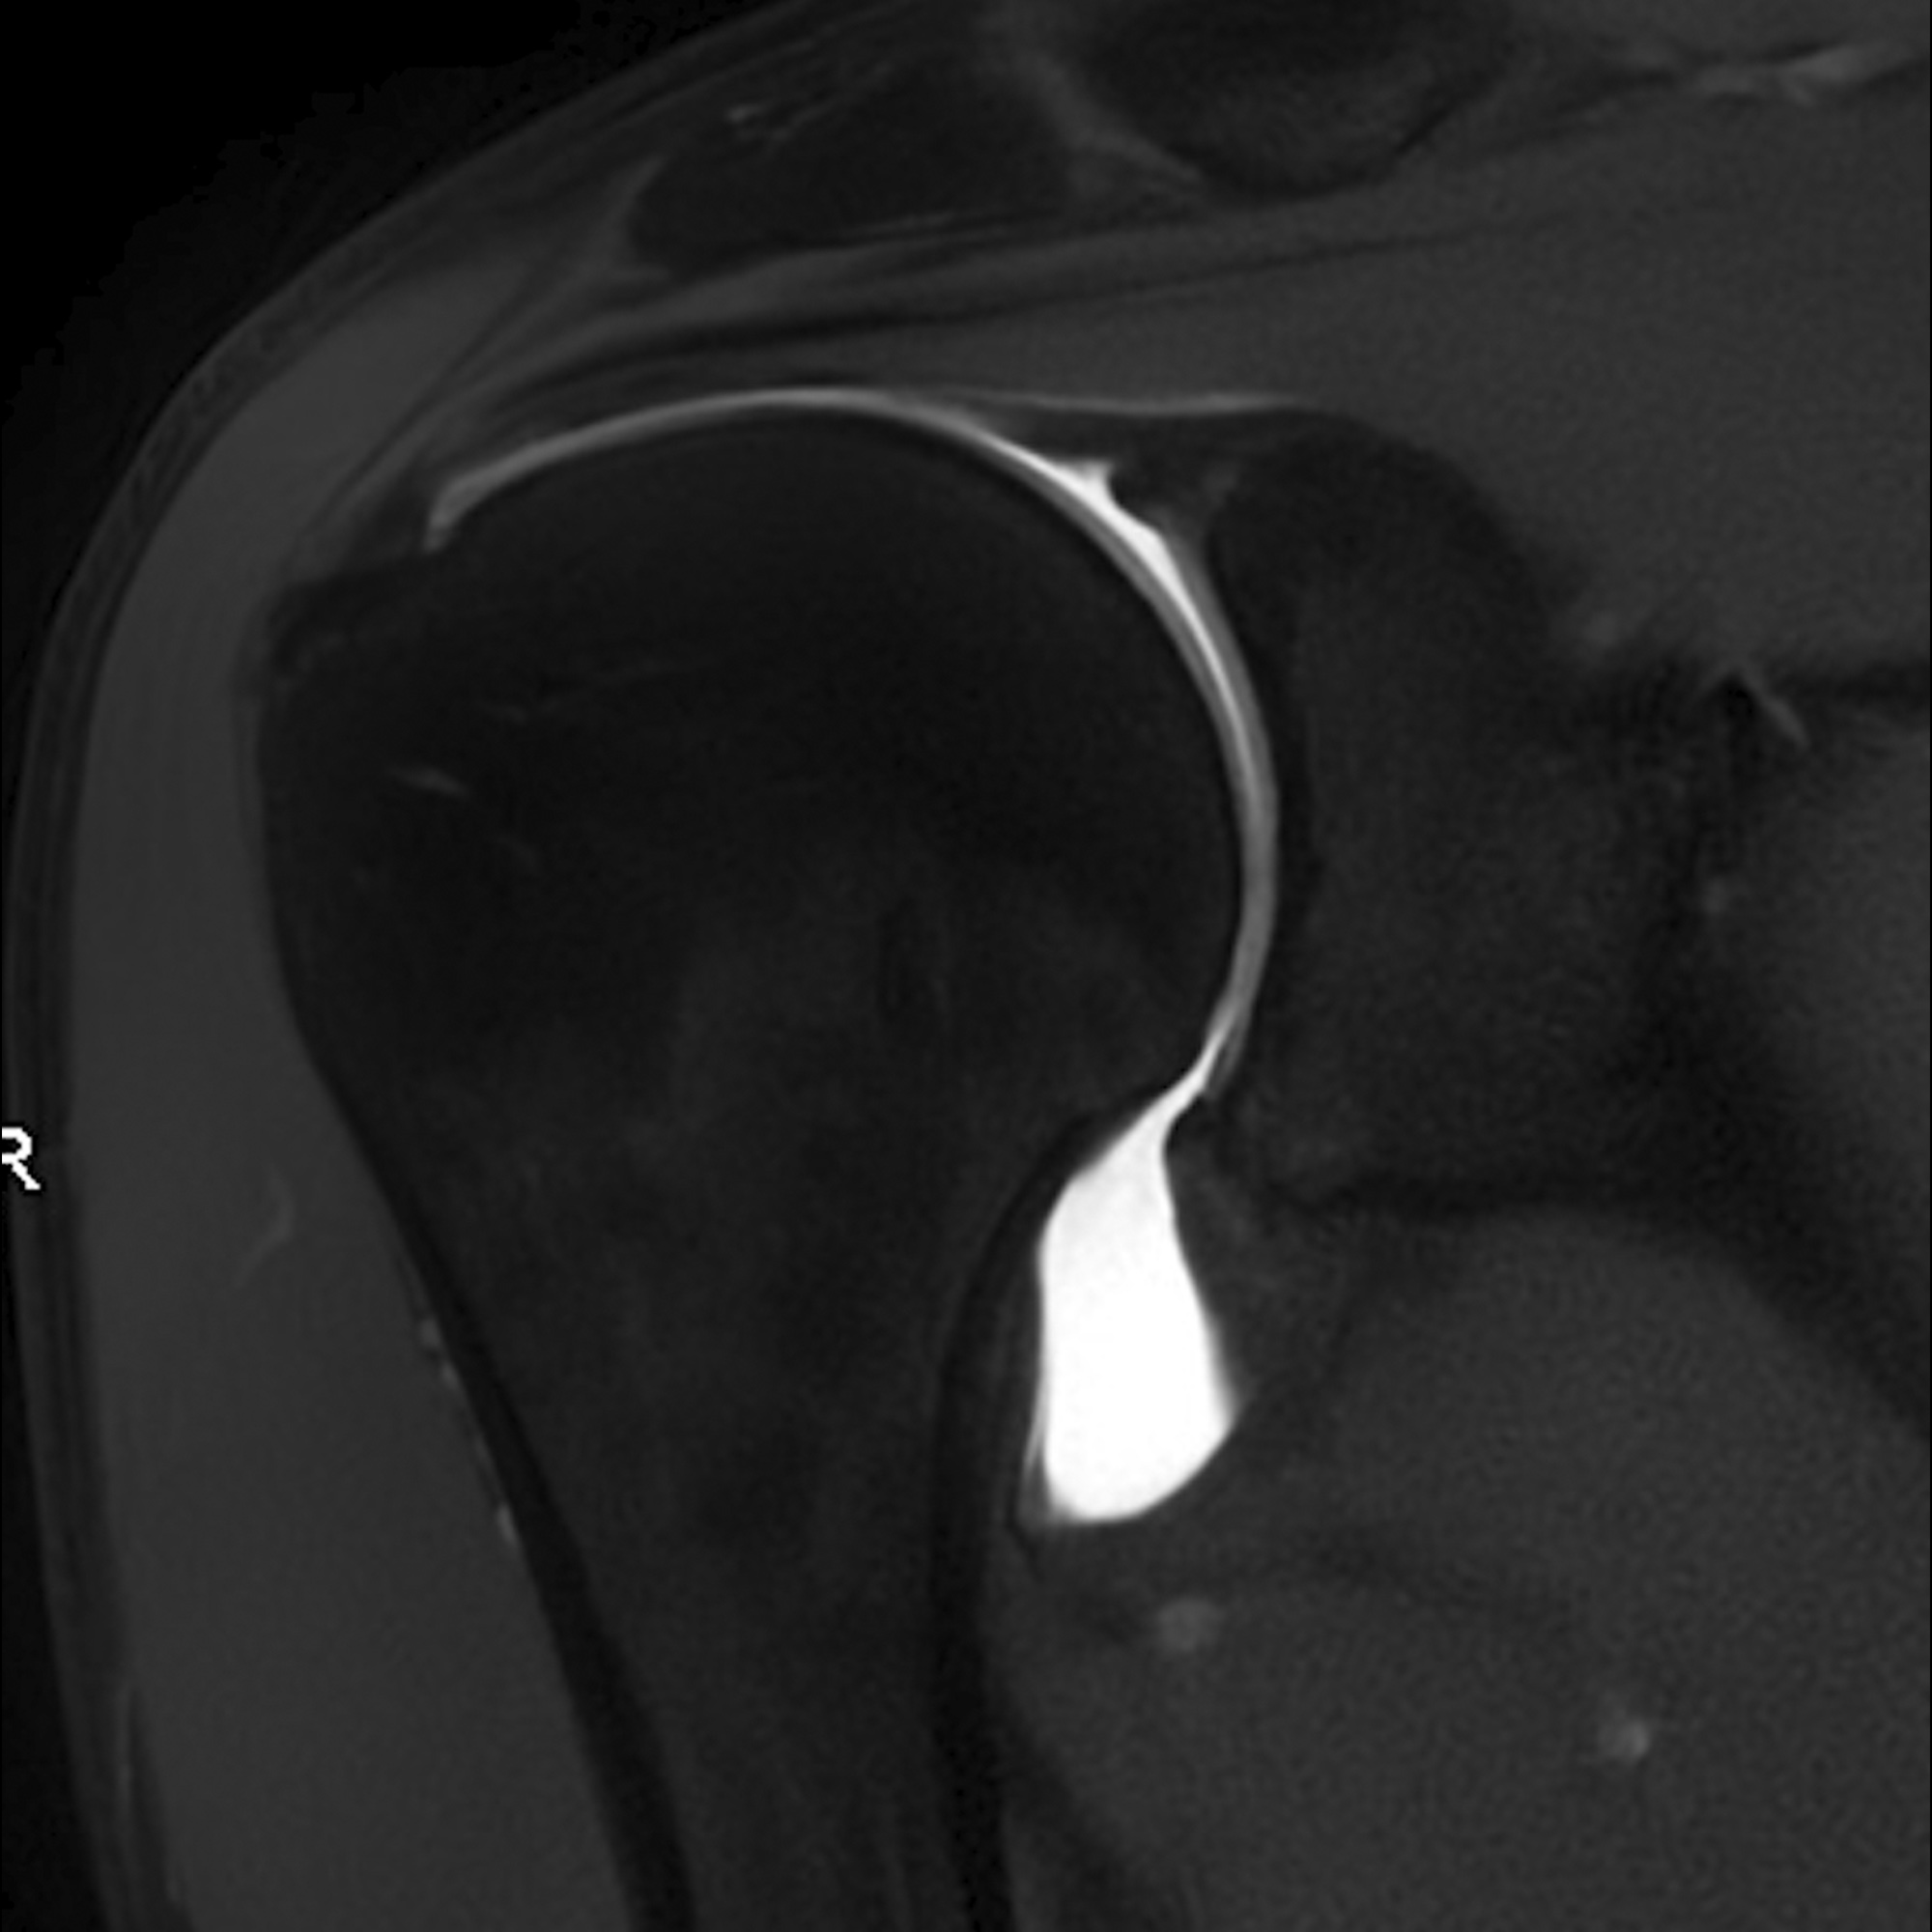

Arthro-IRM images d'examen